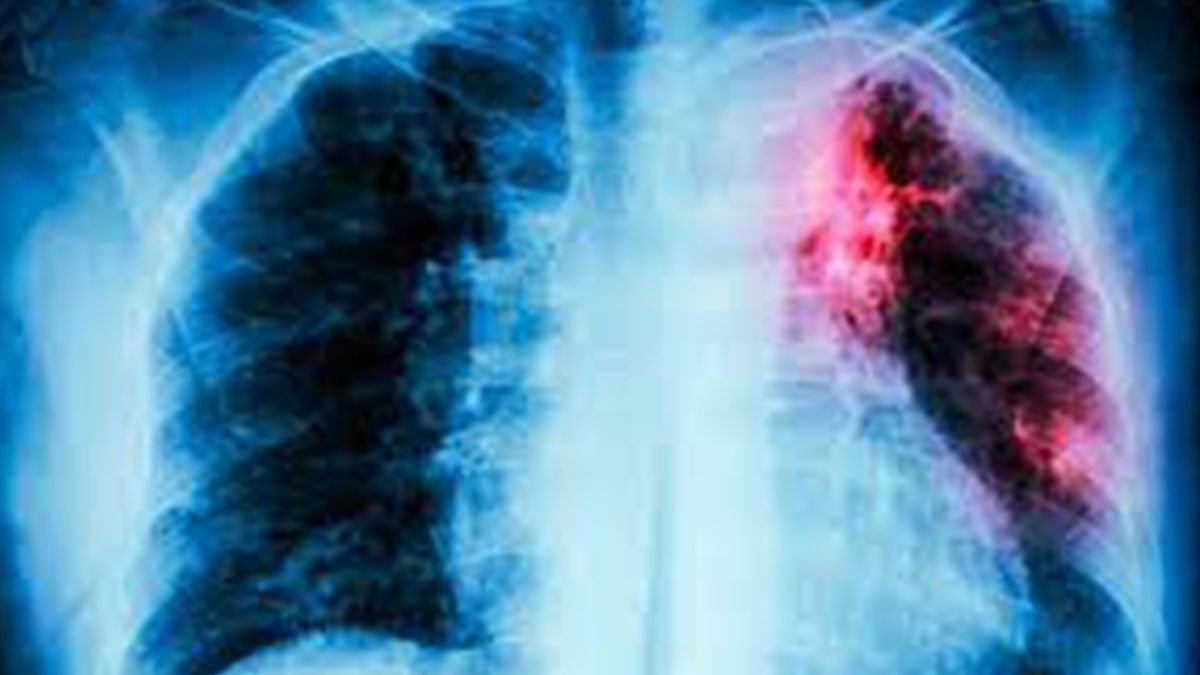

La tuberculosis (TBC) continúa siendo una de las principales causas de muerte por enfermedades infecciosas en el mundo.

Cada 24 de marzo se conmemora el Día Mundial de la Tuberculosis, una jornada que busca visibilizar el impacto sanitario, social y económico de esta enfermedad. Causada por la Mycobacterium tuberculosis, esta infección se transmite por vía aérea, principalmente a través de gotitas que quedan suspendidas en el aire cuando una persona con tuberculosis pulmonar activa tose, estornuda o habla. Aunque muchas veces se la relaciona con contextos vulnerables, puede afectar a cualquier persona, independientemente de su condición social.